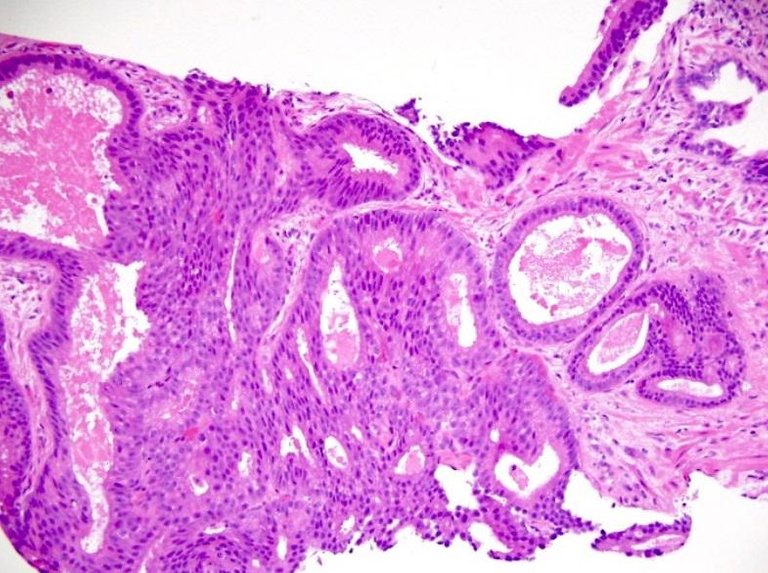

Podsumowując mamy pana, który zgłosił się z powodu problemów z oddawaniem moczu. Pobraliśmy mu co najmniej dwa razy krew. Zbadaliśmy per rectum, USG oraz zrobiliśmy dwanaście otworków w odbytnicy, przez które pobrano wycinki prostaty. Wynik histopatologiczny to Adenocarcinoma acinare prostatae (Gleason 4+4). Teraz powstaje pytanie, co zrobić dalej. Zoperować? Naświetlić? Podać hormony? Nic?

Ryc. D – prawidłowa struktura gruczołowa uległa zatraceniu, co doskonale widać. W miejsce kółeczek pojawiają się zwarte struktury, które nawet nie przypominają dawnej architektury tkanki.